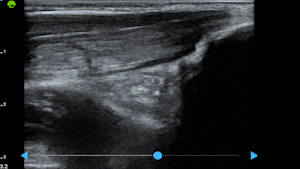

Real-Time Visual Guidance

Dynamic, multi-planar probe positioning assistance overlaid directly on the ultrasound image

Automatic Quality Assessment

Real-time quality scoring with percentage indicators ensures every captured image meets diagnostic standards